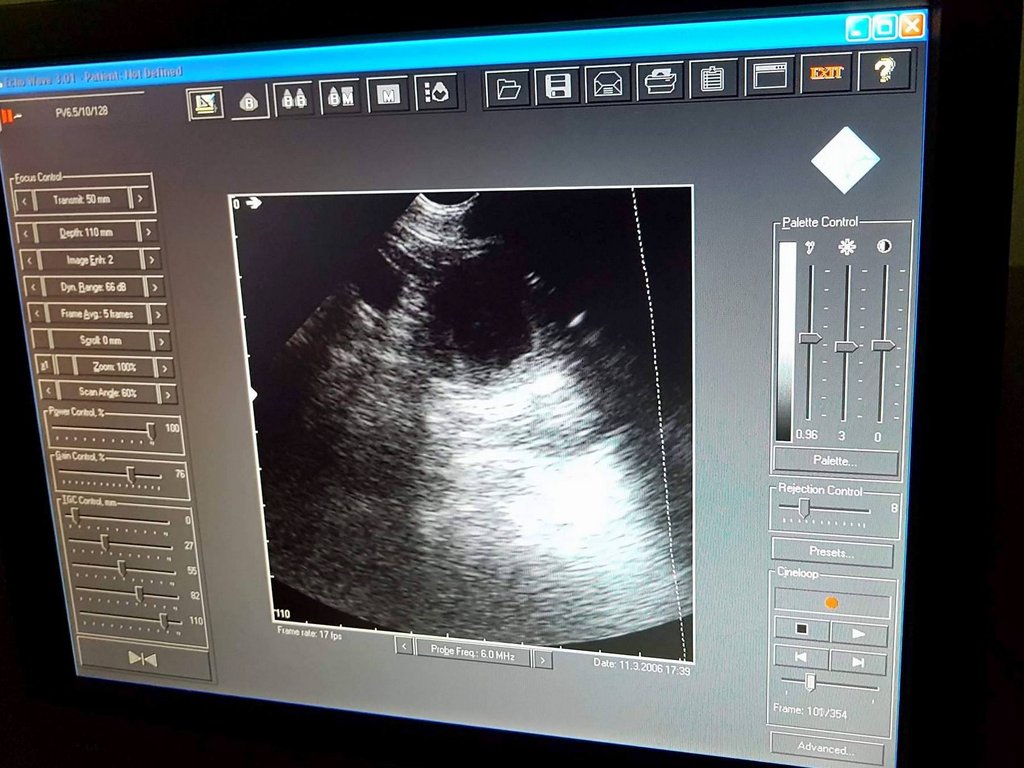

sono Ginger 2192017